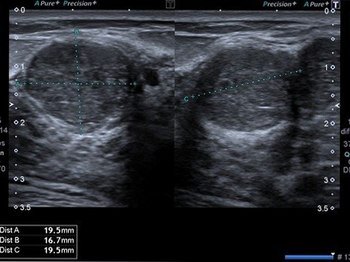

Lenf bezleri doğuştan vücudumuzda bulunan ve vücudumuzun mikroplara karşı ilk koruyucu tabakalarıdır. Enfeksiyon ajanları ile karşılaşınca büyürler, enfeksiyon tedavi edilince ya da vücut tarafından etkisiz hale getirilince küçülürler. Ayrıca lenf bezleri bir takım hematolojik kan hastalıkları (lenfoma, lösemi vb.) ve bazı kanserlerde de etkilenirler ve büyürler. Büyümüş bir lenf bezinin enfeksiyona mı yoksa kansere mi bağlı olduğunu anlamakta ultrasonu çok önemli bilgiler vermektedir. Buna göre de hastanın takip, medikal tedavi ve biyopsi kararı verilmektedir.